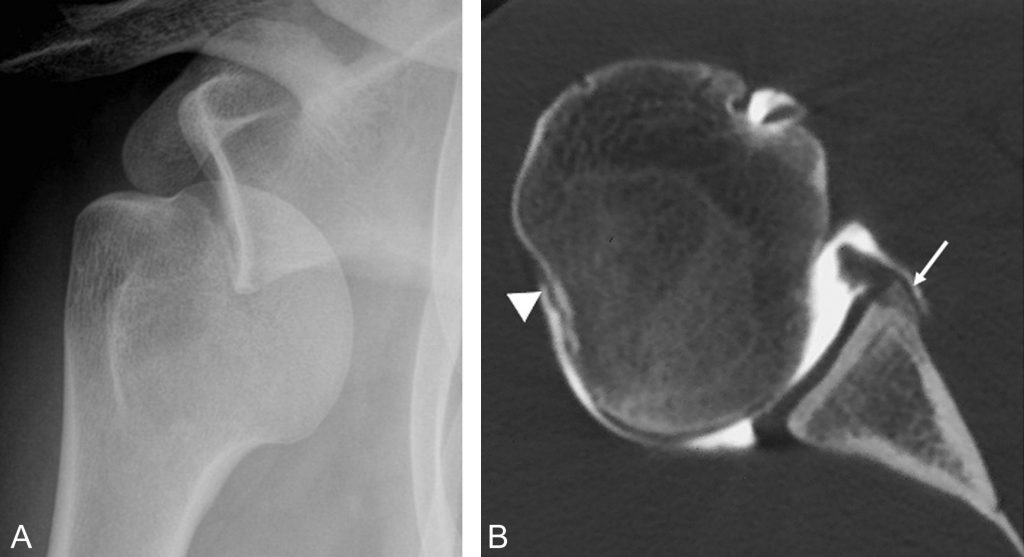

La radiographie montre en cas de luxation antéro-inférieure la perte des rapports normaux entre la tête humérale et la glène (figure 79.5). La glène est vide ; la tête humérale se projette sous le processus coracoïde. Sur le cliché de face, il existe une superposition entre la tête et le rebord inférieur de la glène.

On recherche une encoche de Hill-Sachs (fracture par impaction du tubercule majeur) et une fracture du rebord antéro-inférieur de la glène (lésion de Bankart).

Fig. 79.5 Luxation antéro-inférieure de l’épaule droite.

Radiographie de l’épaule de face (A) montrant un déplacement antérieur et inférieur de la tête humérale. Coupe axiale d’un arthroscanner (B) réalisé à distance de l’épisode traumatique montrant une encoche de Hill-Sachs (tête de flèche) et une fracture du rebord antéro-inférieur de la glène (flèche).

Source : CERF, CNEBMN, 2022.